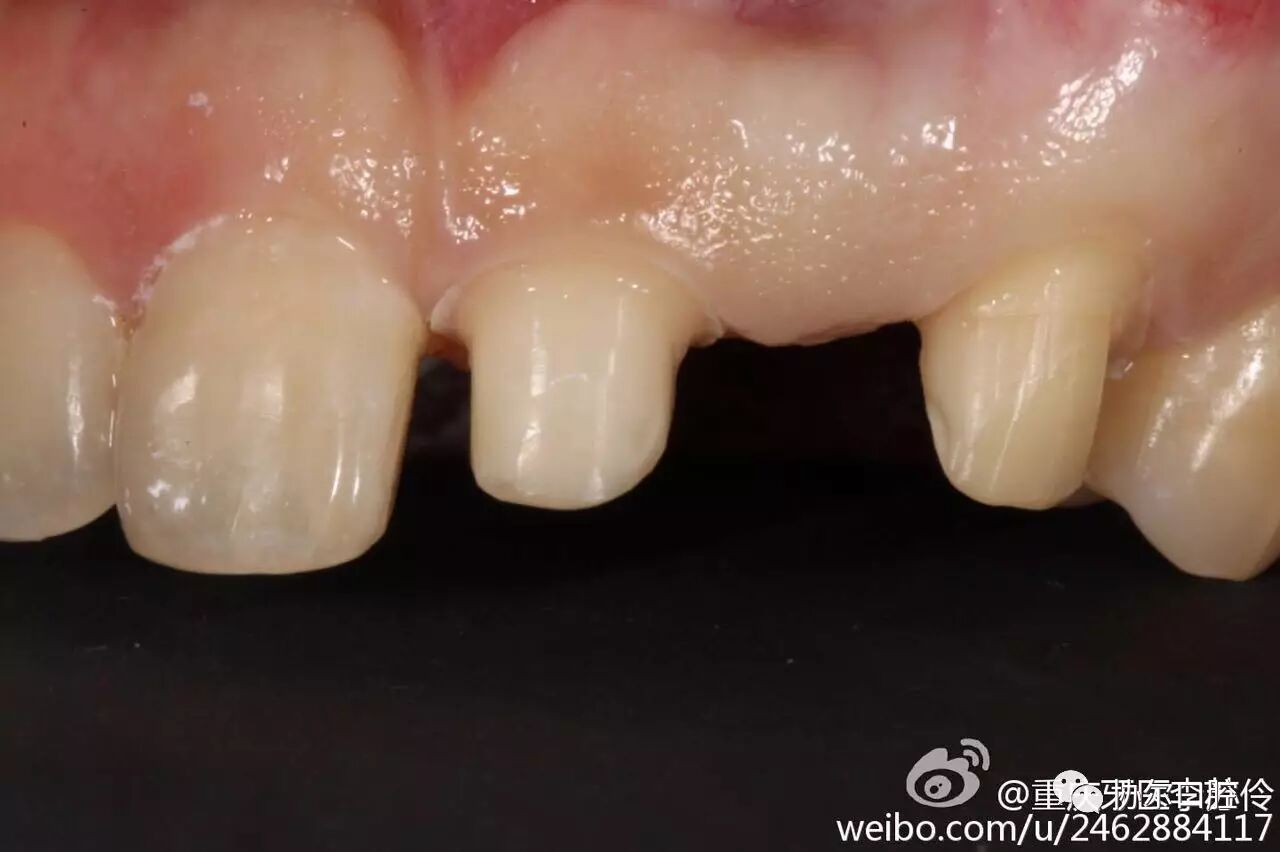

显微镜下精确备牙

让健康牙体组织得到最大限度的保存。

显微树脂微创美学修复

确保所有感染死角彻底清除,最大限度保留正常牙体组织,还原牙齿最原始的形态,让补出的牙齿更加美观、结实耐用!